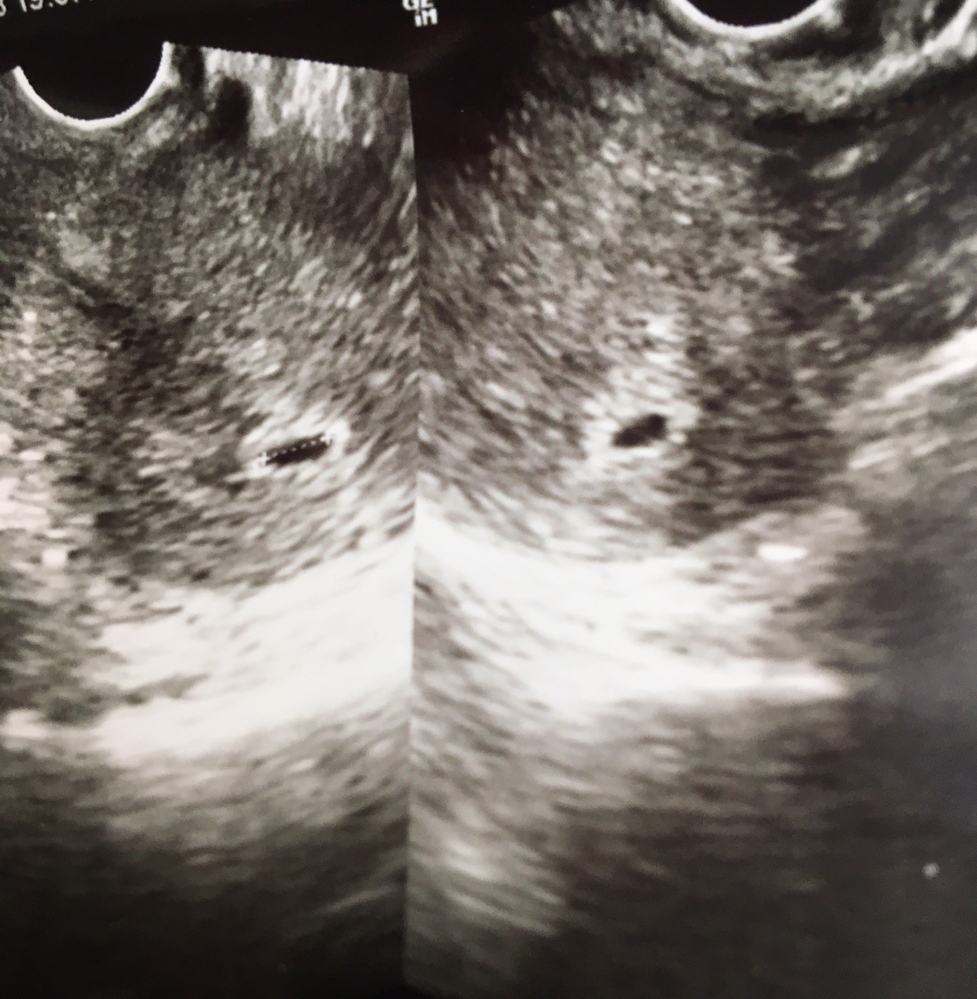

Web妊娠6週の⼤きさ 胎嚢は15cmほど になり、胎嚢の中の白っぽい円も大きくはっきりと見えるようになります。 (参考文献1) その近くに 白く見えるのが赤ちゃん(胎芽)で、まるで宝Web 妊娠6週で胎嚢が見えない、7週でも心拍が確認できなかった話 21年5月30日 / 22年7月26日 娘を妊娠したとき 胎嚢確認も、心拍確認も遅くとても不安でした 暇さえあ

胎嚢は見られたけど 妊娠6週と6日目のものです 先日病院に行き Okwave

Web 妊娠8週目で一気に成長 以下は、Yahoo知恵袋で見つけた質問「胎嚢の成長が遅れていたけど、急成長して無事 」への回答です。 5w0dで受診するも、胎嚢は44mmで、Web妊娠6週 胎児心拍が確認できないといわれました 不妊治療を数カ月していました。 多嚢胞卵巣が原因らしいです。 今回、不妊治療を止め、2カ月後に妊娠が判明しました。 本日、病院Webくろみつさんの妊娠6週目のエコー写真 心臓の動きが確認できてひと安心 エコー画像で振り返る、私に宿った小さな命が大きく育って誕生するまでの記録 おなかの赤ちゃんは元気でいる